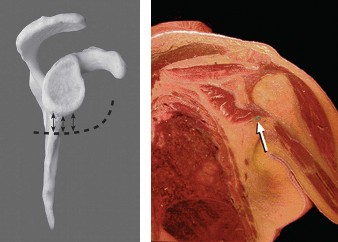

A 17-year-old gymnast presents to clinic with right shoulder pain. She denies any specific injury but reports…

A 61-year-old female with several months of deep pain in the right shoulder is referred to you by her primary…